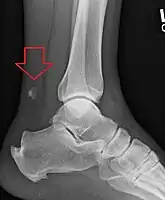

Radiography can also be used to indirectly identify Achilles tears. Radiography uses X-rays to analyse the point of injury. This is not very effective at identifying injuries to soft tissue. X-rays are created when high energy electrons hit a metal source. X-ray images are acquired by utilising the different attenuation characteristics of dense (e.g. calcium in bone) and less dense (e.g. muscle) tissues when these rays pass through tissue and are captured on film. X-rays are generally exposed to optimise visualisation of dense objects such as bone while soft tissue remains relatively undifferentiated in the background. Radiography has little role in assessment of Achilles' tendon injury and is more useful for ruling out other injuries such as calcaneal fractures.[13]

Achilles tendon avulsion seen on plain X-ray -